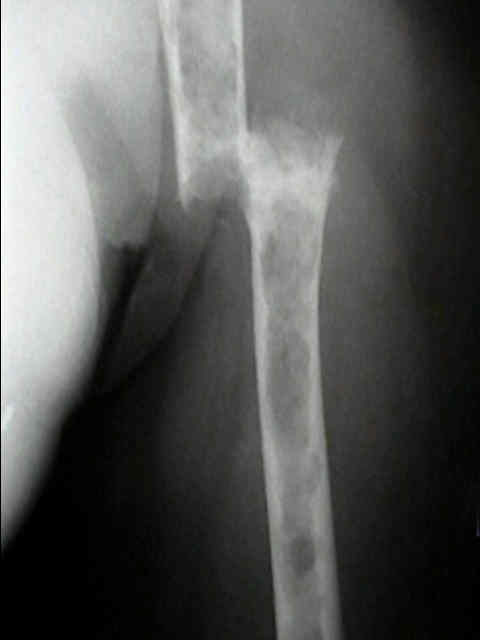

Humerus 10

Humerus 11

Surgical Fixation

mmyl1 mmyl2